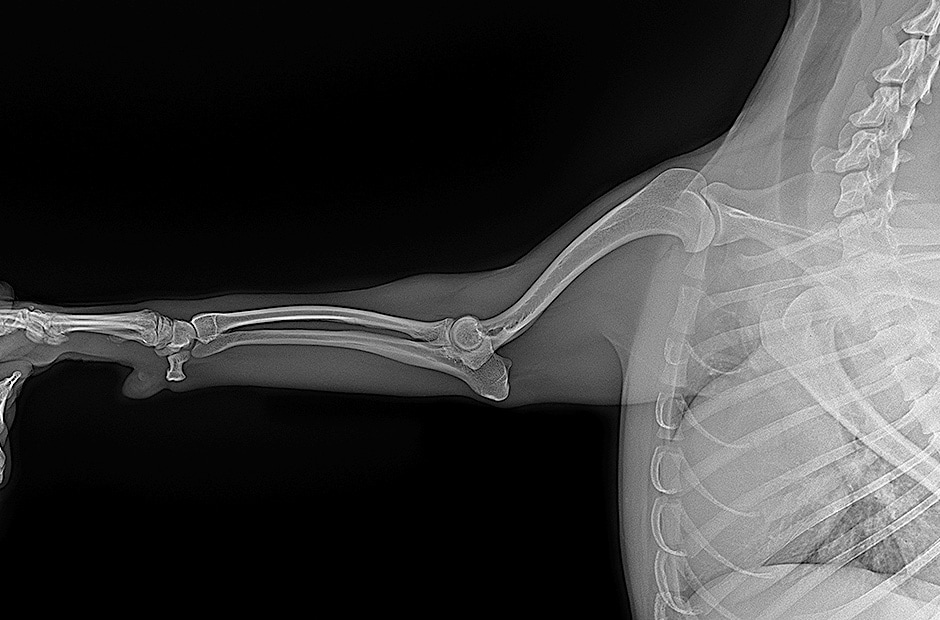

Capteur plan 17x17"

Radiographie Générale